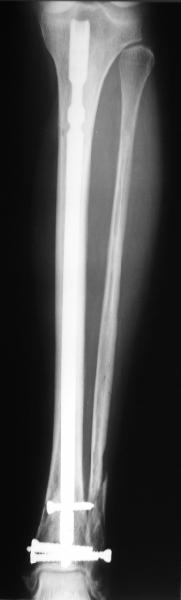

A typical case is attached, also an image with intra-op reduction obtained by a small wire distractor, in the moment of insertion a Poller wire in AP direction. Fixation by a SIGN nail. Despite the fibula was not fixed healing was obtained with the unchanged alignment.

I am just trying to illustrate that prevention of 1)tibial valgus and 2)loss of reduction can be provided without fibular plating. Small changes of conventional nailing techniques allow to maintain reduction of the tibia reliably without adjunctive fibular stabilization.